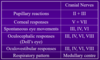

How is brianstem function tested?